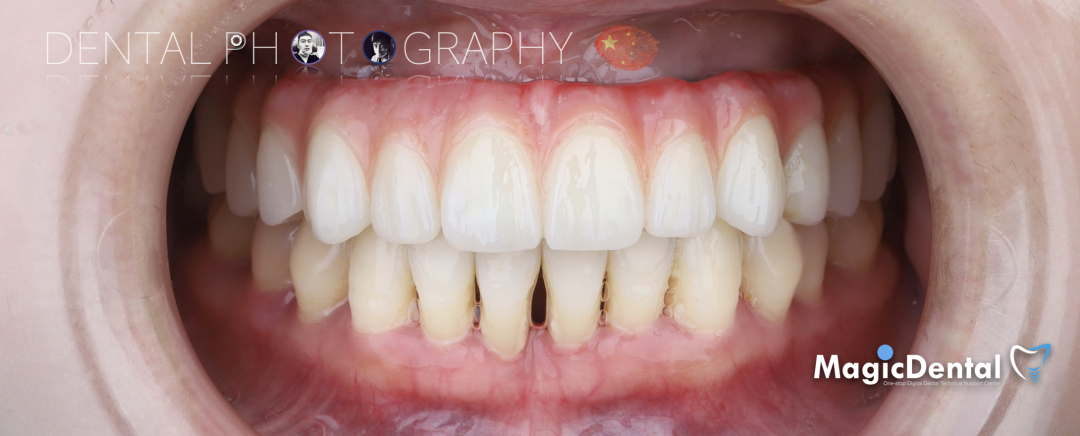

患者术前口内及面相照片

患者:32岁女性患者。

主诉:牙齿松动要求治疗。

现病史:患者两年前发现牙齿逐渐松动,近一个月左上前牙脱落,且上颌牙齿无法咀嚼,现来我院就诊要求治疗。

既往史:既往体健,无其他系统病史,否认重大疾病史,有口腔拔牙史。

口腔检查:口腔卫生差,全口牙龈红肿,牙颈部大量牙结石附着,伴有不同程度附着丧失,牙周探针深度普遍大于8mm,上颌牙列I~III°松动。

术前术后对比